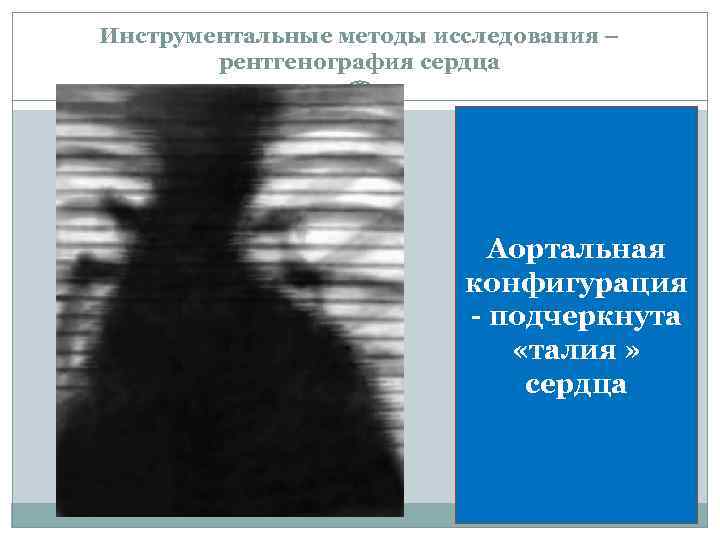

Инструментальные методы исследования – рентгенография сердца Аортальная конфигурация - подчеркнута «талия » сердца